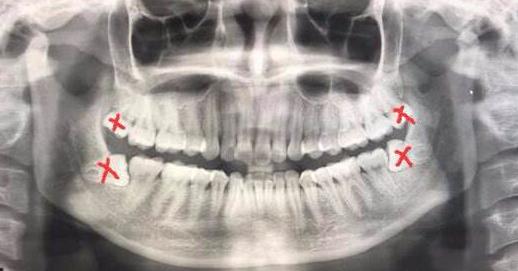

如圖所示,**有上下左右4顆智齒